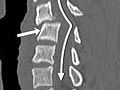

La tomografía computarizada (CT, por sus siglas en inglés) utiliza rayos X para tomar imágenes detalladas de la columna vertebral y las vértebras del cuello (columna cervical), la parte superior de la espalda (columna torácica) o la parte baja de la espalda (columna lumbosacra).

CT de la columna vertebral

Normal:

Los huesos de la columna ( vértebras) son normales en forma, número y alineación.

Los discos y las articulaciones que sostienen la columna vertebral son normales.

El canal espinal tiene un tamaño y una forma normales.

Si se usa material de contraste, este fluye de manera pareja por el canal espinal. No hay ningún estrechamiento u obstrucción del canal espinal.

Ninguno de los nervios que salen de la médula espinal está comprimido o pellizcado. No hay crecimientos ni bultos.

Anormal:

Hay huesos de la columna (vértebras) faltantes, dañados o mal alineados.

Uno o más discos podrían estar dañados. Se detectan uno o varios discos herniados.

El flujo del material de contraste por el canal espinal está restringido u obstruido, lo que indica el estrechamiento del canal ( estenosis espinal).

Las vértebras muestran signos de artritis o problemas óseos causados por la osteoporosis.

Hay una afección que ha estado presente desde el nacimiento (afección congénita) en la columna vertebral o en las vértebras.

Se detecta un absceso o un tumor en la columna vertebral.